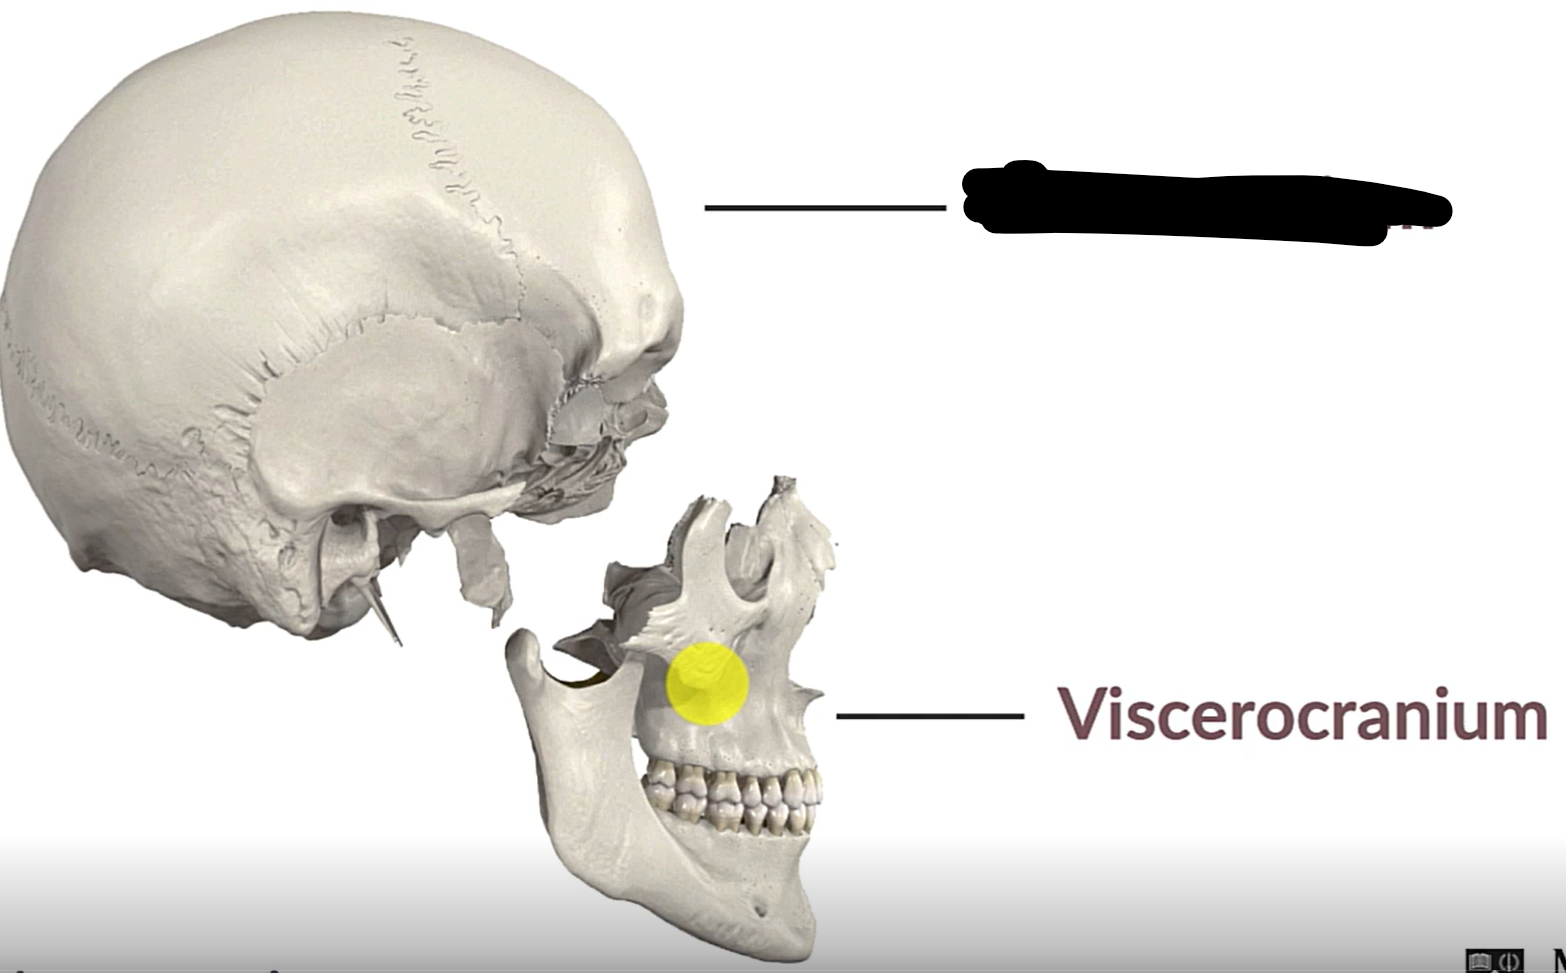

Neurocranium

Viscerocranium